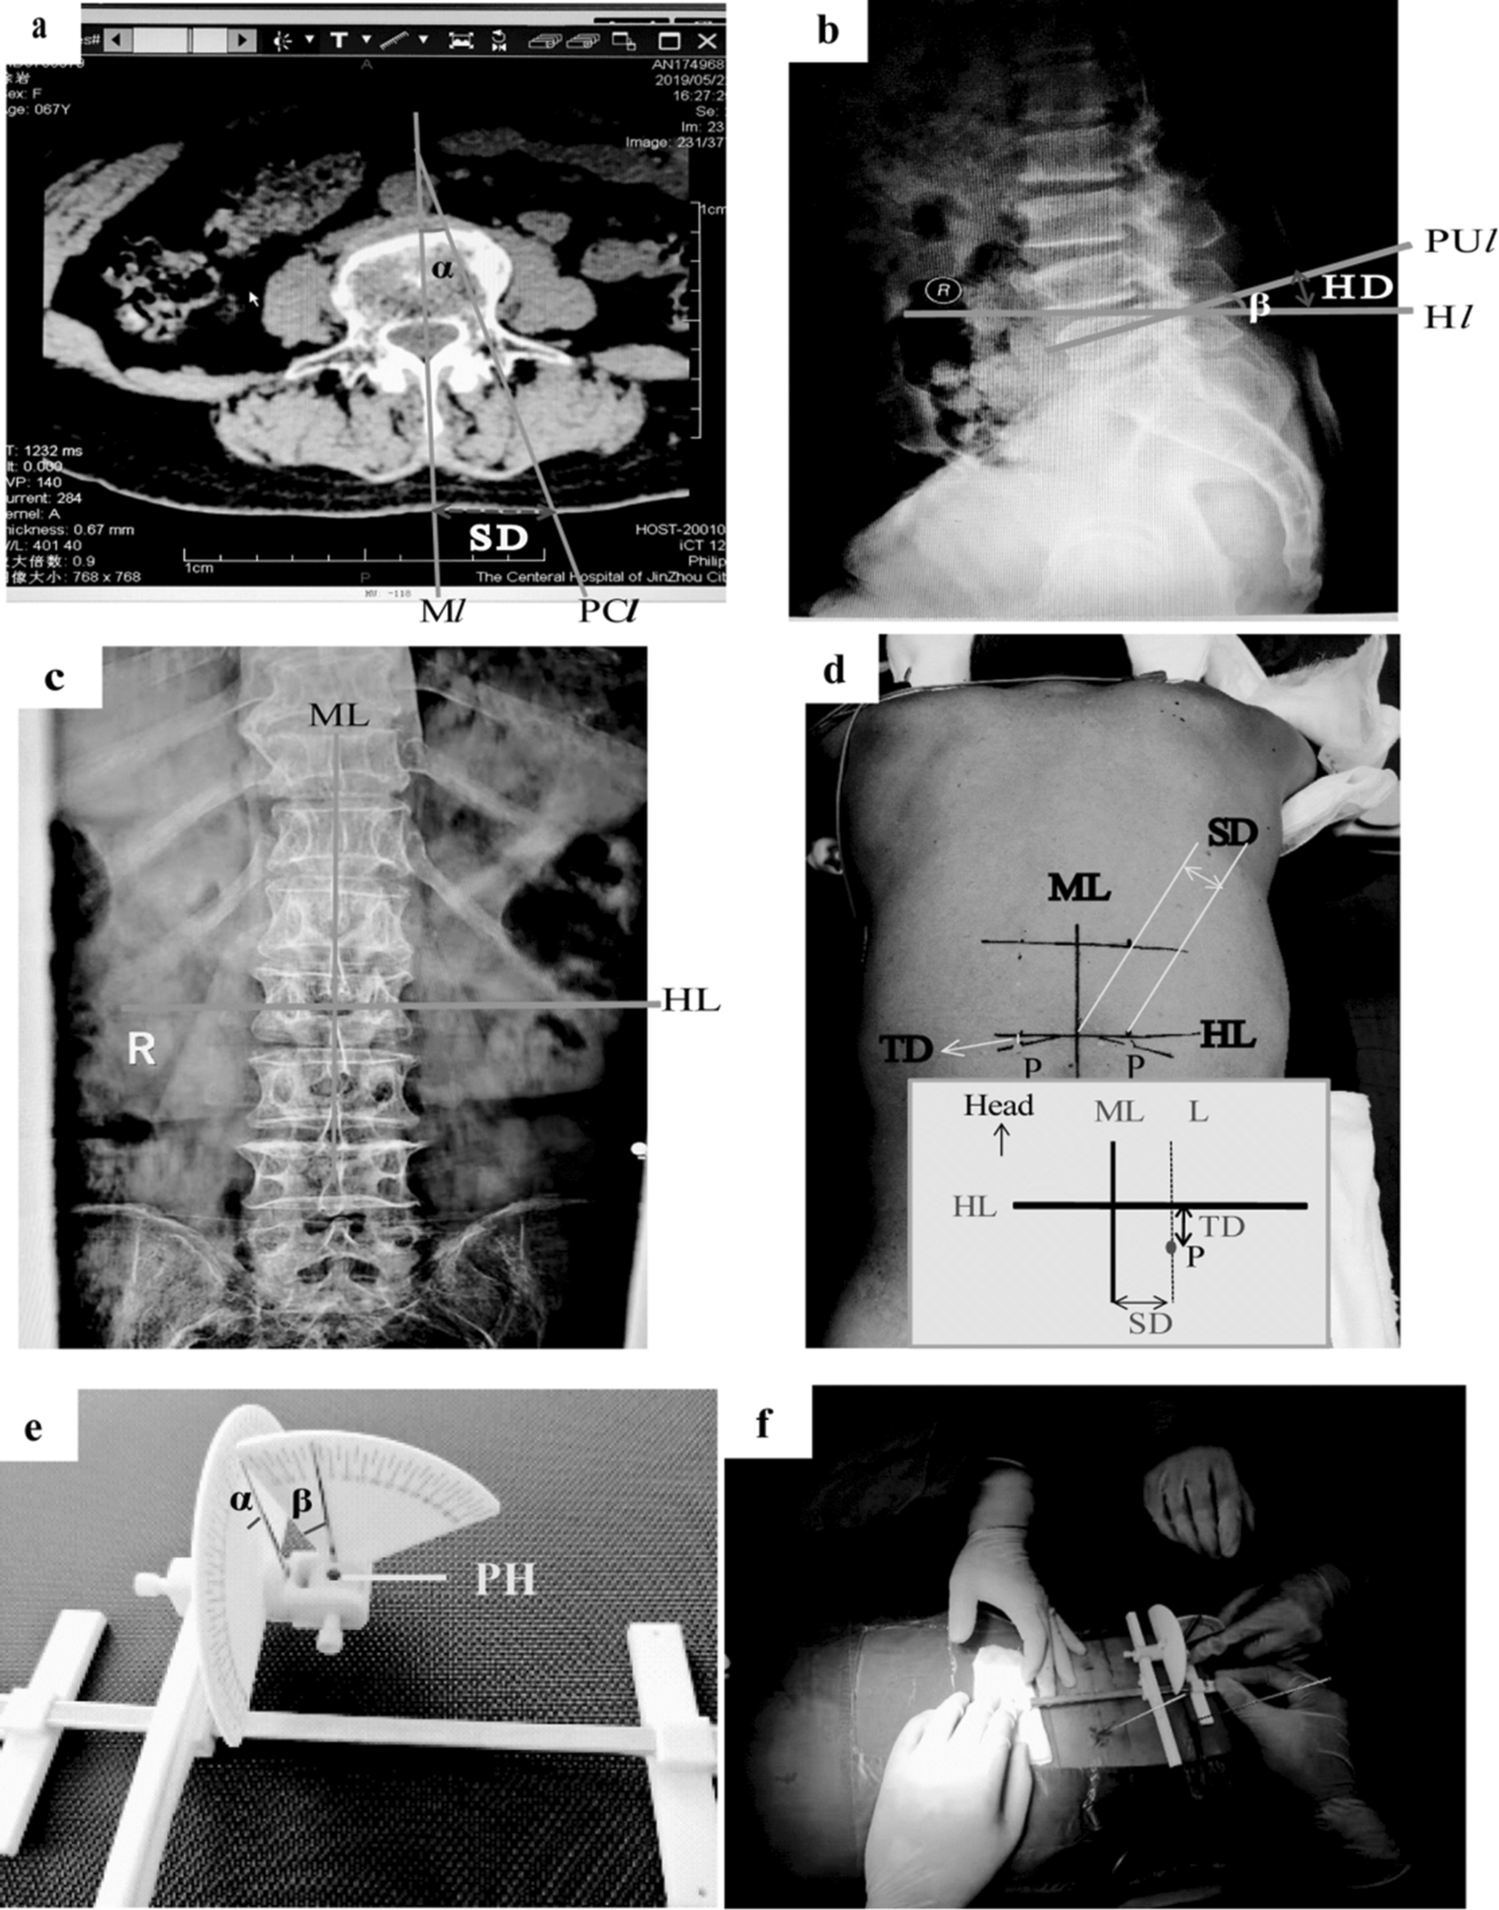

Figure 2

From: Application of a new percutaneous multi-function pedicle locator in minimally invasive spine surgery

Four lines, two distances, and two angles presented for application of the locator in a surgery. Graph (a) show Ml and PCl lines, SD, and angle α in a cross-sectional CT image; Graph (b) displays PUl and Hl lines, H/TD, and angle β in a lateral X-ray image. Graph (c) illustrates ML and HL lines on the body surface using an X-ray image. Graph (d) shows ML and HL lines, SD and H/TD, and point P on the body surface. Graph (e) depicts angles α and β on the two scale dials of the locator. Graph (f) shows the practical utilization of the locator. Ml and ML, linear median posterior; PCl, pedicle channel line; PUl, needle entry point on pedicle; Hl and HL, horizontal lines; SD, side opening distance; H/TD, head or tail tilt distance; angle α, extroversion angle; angle β, head or tail tilt angle; P, percutaneous puncture point; PH, a needle passing through the skin to the target point (pinhole surgery).